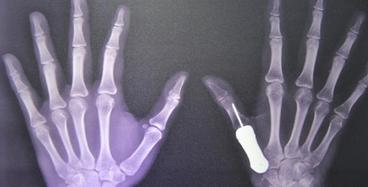

近日,全球首例3D打印鈦金屬假體植入人體手掌手術(shù)在泰國曼谷Phramongkutklao醫(yī)院獲得成功。